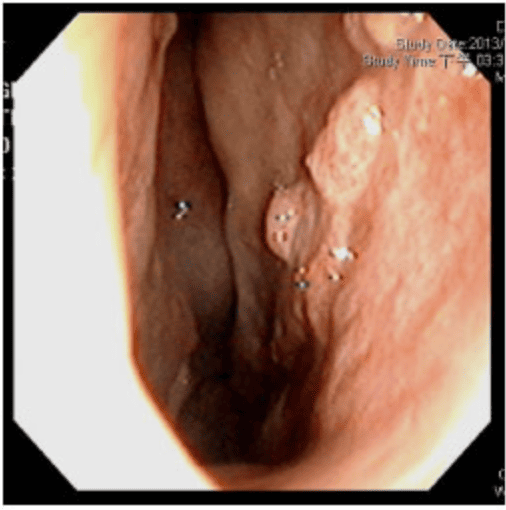

▲透過手術前後鼻阻力圖對照,術前右側鼻阻力線都接近水平線,表示呼吸阻力極大,術後鼻阻力線恢復正常曲線,接近兩邊對稱,表示呼吸恢復暢通,傷口也恢復良好。